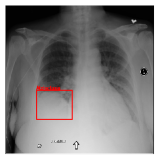

CXR8 [21] is one of the most commonly accessible radio-logical examination for many lung diseases. The data consists of 112,120 images collected by 30,805 patients. As shown in Table I, nine class labels of normal state and eight diseases including cancer are defined for classification. The data is divided into training set and test set, and the classification accuracy and ROC curve with several well-known deep network such as VGG16, GoogLeNet, and ResNet, are reported on the original paper [21]. In addition, 984 Bounding Boxes (B-Box) are provided for localization. Fig. 5 shows image examples of CXR8. The red rectangle in the image shows given B-Box.